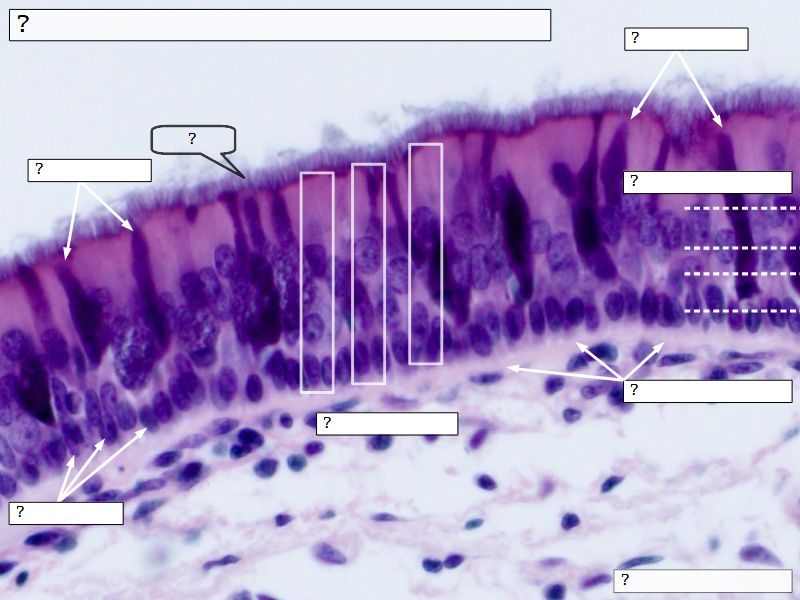

Fill in all the missing labels, and assess as you move through the slides. Answers on the down slide. It is important to do this using pen and paper, and not just glance through the images.